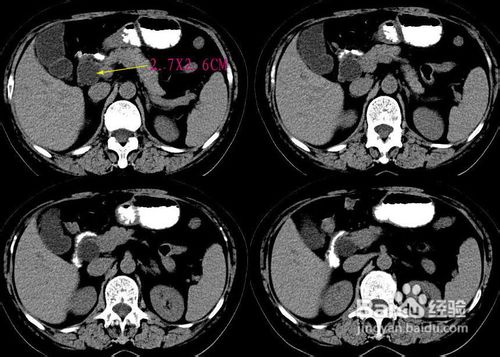

葡萄胎的诊断一经确定后,就应该决定治疗方式,尽早治疗。但是治疗前,胸部X光,心电图和血液常规检查都要做。葡萄胎的主要治疗方式有下列四种:

通常生产后或流产后,2-3个星期hCG会降至正常值。但是葡萄胎在治疗后,则须2-3个月才能降至正常值。完全性葡萄胎在治疗后,80%会恢复正常,15%变成侵袭性葡萄胎,5%发展成绒毛膜癌。部分性葡萄胎则只有5%发展成恶性肿瘤。因此不论何种葡萄胎在治疗后,均须持续追踪一年,以防恶性化。并且在追踪的一年内,不能再次怀孕,以免复发。